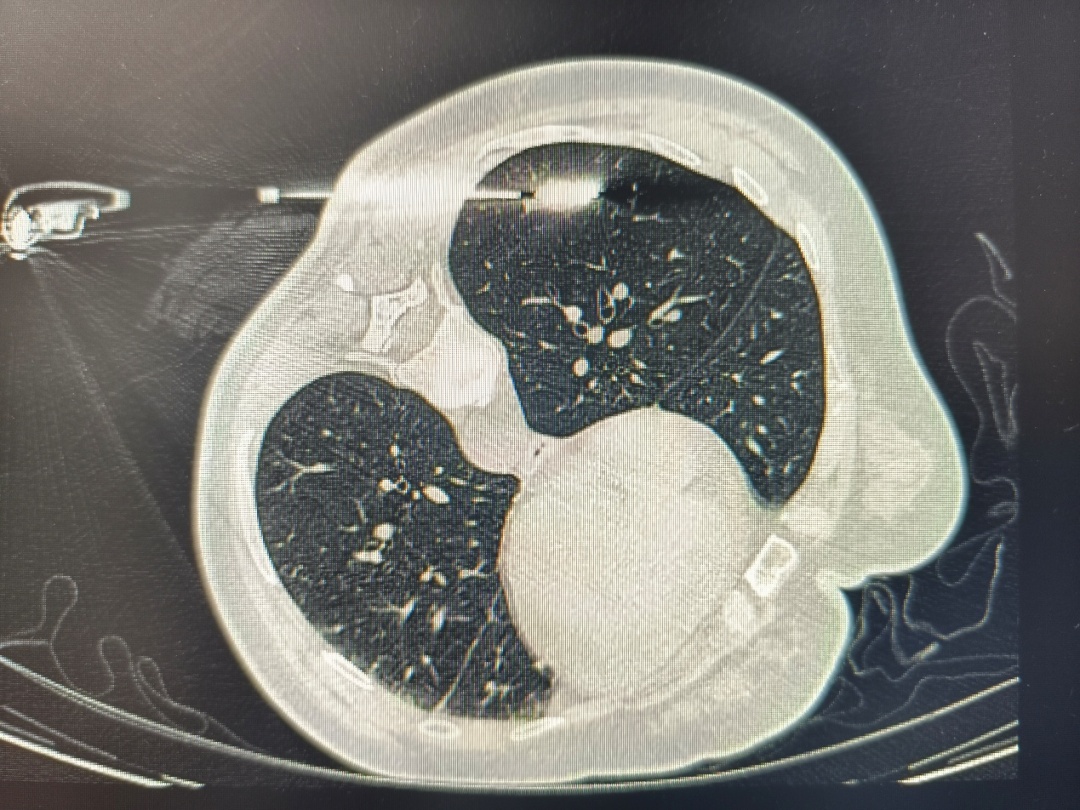

1. 影像观察“以貌取结”

大小:

结节越大,恶性风险越高。≤5mm的微小结节大多良性。

长相:

边缘光滑的常为良性;边缘有“毛刺”、分叶或胸膜牵拉的需警惕。

质地:

纯磨玻璃结节多为良性或极早期癌变;混合型磨玻璃结节若实性成分增多,风险上升。

纯磨玻璃肺结节

混合性肺磨玻璃结节

实性肺结节